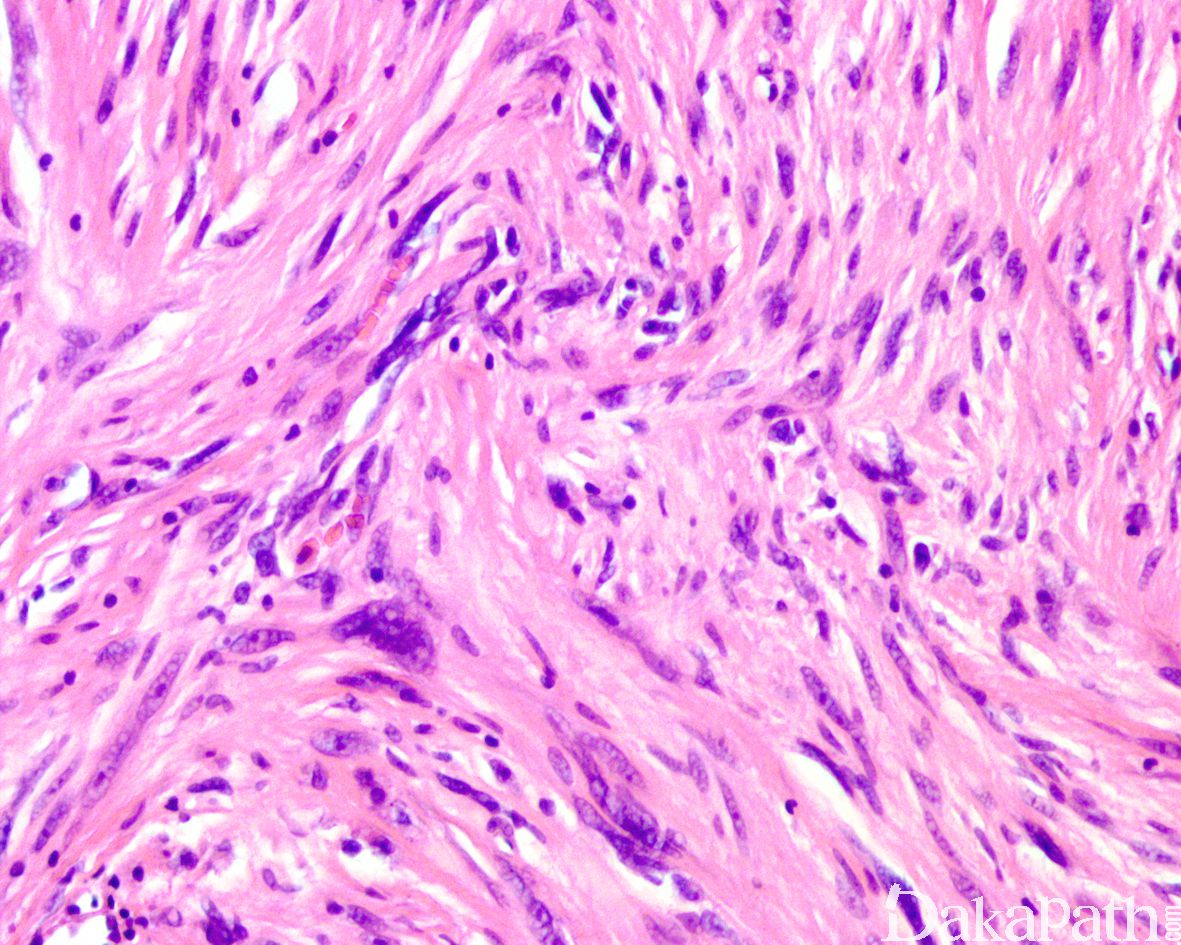

镜下肿瘤中等富于细胞,主体位于皮下组织内,偶见于真皮内;

总体上肿瘤呈膨胀性生长但伴有不同程度的周围脂肪浸润或真皮累及;

瘤细胞梭形至上皮样,呈束状或实性片状排列,胞浆丰富呈颗粒状、原纤维状或玻璃样改变,部分表现为黄瘤样胞浆;

大多数肿瘤细胞核具有明显的多形性,常见奇异性核或多叶核以及核内假包涵体,核染色质深伴 1 至 2 个明显的核仁;

尽管肿瘤富于细胞且伴有明显的非典型性核,但核分裂像非常罕见,大多数<1 个/50 高倍镜视野,无非典型核分裂像,无肿瘤性坏死;

间质内可见分支状薄壁的毛细血管以及散在的慢性炎细胞和肥大细胞浸润。